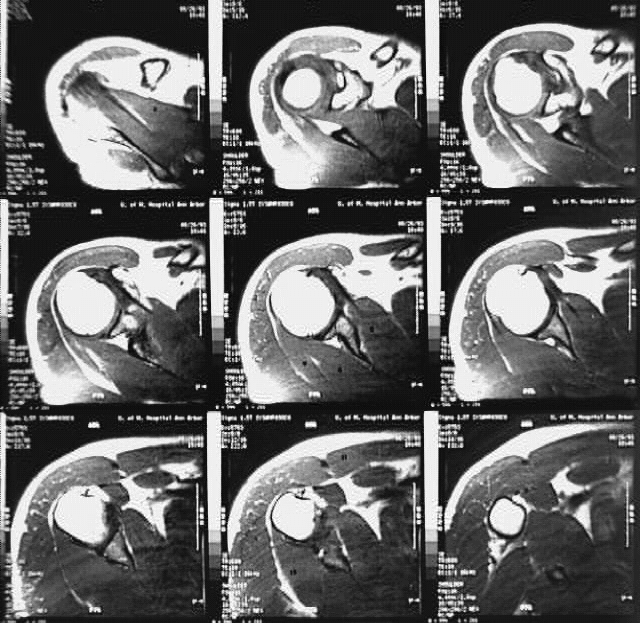

Radiology Images

Upper Limbs:Shoulder MRI Cross: